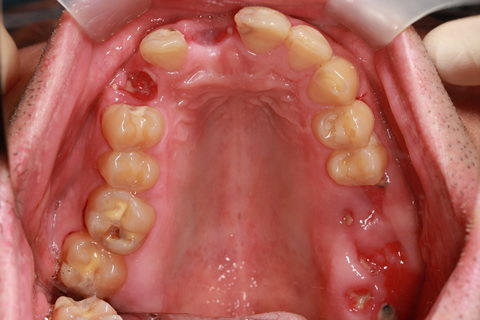

症例4

- 年齢・性別

- 60歳

- 治療期間

- 6ヶ月

- 抜歯

- 残根抜歯のみ

- 治療費

- 198万円

- 備考

- 右上5.6 右下5 左下4.5.6欠損

- 治療内容

- 6本のインプラントを右左側に2回に分けて埋入

- 施術の副作用(リスク)

- オペによる知覚障害。インプラントによる歯肉炎。インプラント脱落。